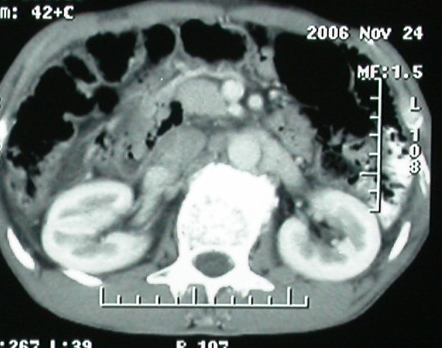

ct表现:1,胰腺钩突后方肿块,不均强化,中心密度低,钩突及门静脉前移。2:肝右后叶不均强化灶,突出肝表面,3:胆囊明显增大,肝内胆管及肝总管内积气。4:腹腔内少量积液。

胰头后方肿块,周边强化,胰头受压推移,肝脏右后叶异常强化灶,首先考虑肝癌后腹膜淋巴结转移;2、肝内胆管积气。

手术结果:

肝脏尾状叶肝癌(沿肝十二指肠韧带向下韧带内生长,门腔间隙外压增大),大结节性肝硬化,胆囊积脓,胆道感染。术中见肝外胆道2cm直径,肿瘤向前压迫胆管至扁平状态。